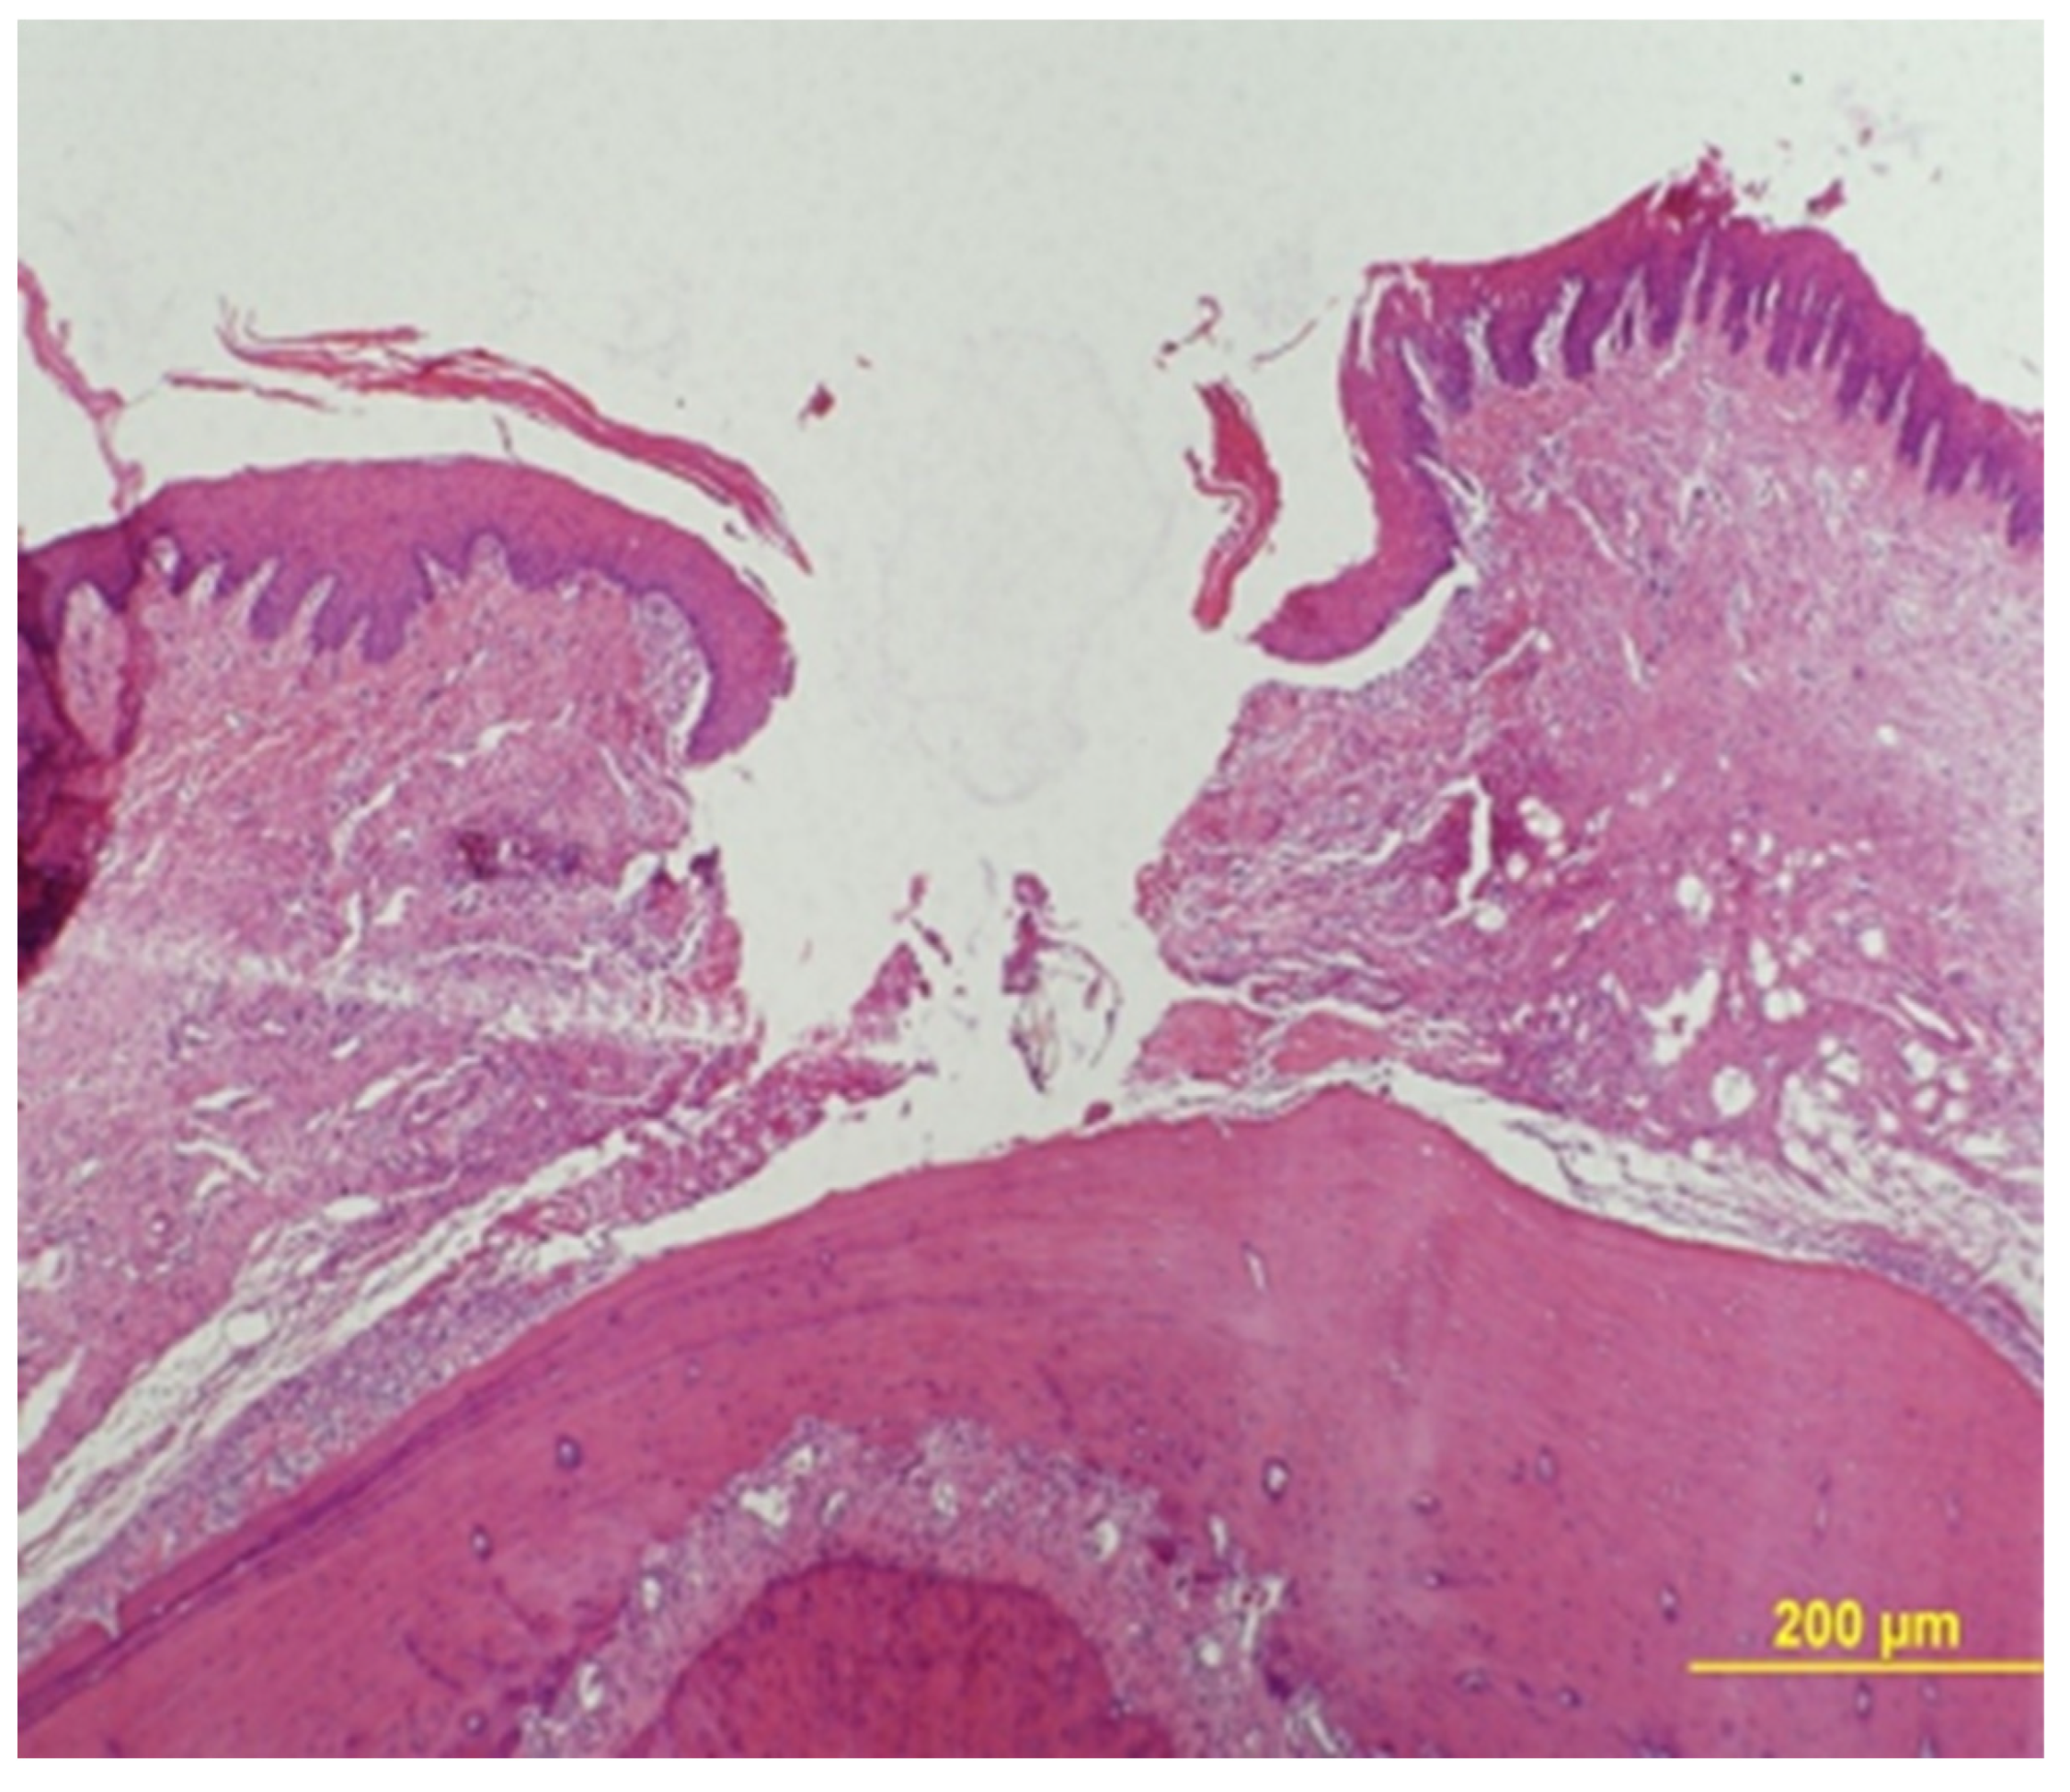

Epithelial Gap Measurement

Epithelial gap was measured under a ×40 magnification using an Olympus BH-2 light microscope (Olympus, Tokyo, Japan). The gap zone was defined by lack of wound tissue and its width was measured between two parallel lines that were drawn tangentially to the tissue that bordered the gap at its both sides (Figure 3).

A mean of all measurements in 2 serial sections were calculated. The results are presented as the mean ± standard deviation (SD) for each of the two time frames (7 and 14 days) of the study groups.

Figure 3. H&E staining for measurement of epithelial gap distance (×40).